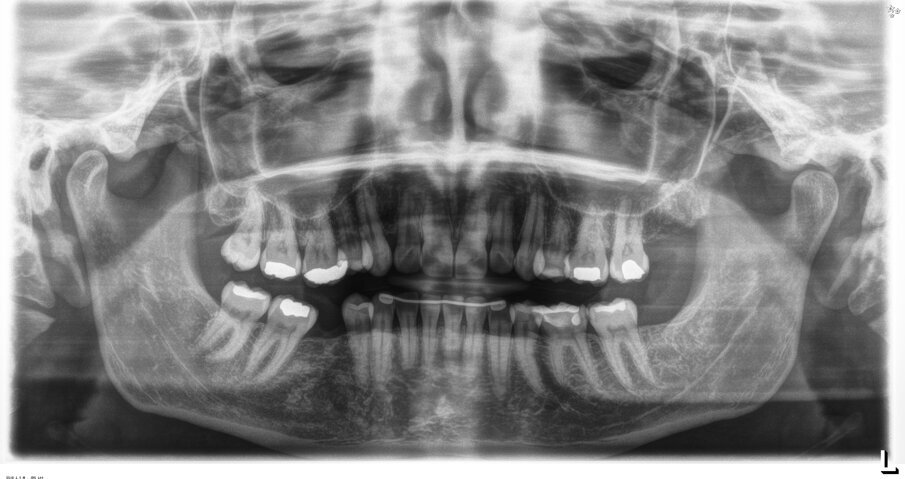

L’esame ortopantomografico (Fig. 3) non ha evidenziato patologie in atto e confermava l’aumentato tipping del secondo e del terzo molare inferiori di destra. La paziente non riferiva alcun disturbo a carico delle articolazioni temporomandibolari. Nella pianificazione del trattamento la paziente è stata informata della presenza di una malocclusione di seconda classe monolaterale per la quale è stata proposta una risoluzione mediante distalizzazione dell’emiarcata superiore di sinistra e uprighting degli elementi 4.7 e 4.8. È stata inoltre informata che la sovraeruzione dell’elemento 1.6 non consentiva di riabilitare l’edentulia in maniera ottimale. La durata del trattamento ortodontico proposto era stimata in 18- 24 mesi. La paziente ha preferito non procedere con un trattamento ortodontico onnicomprensivo, ma ha accettato la proposta alternativa di un trattamento breve con allineatori trasparenti al fine di effettuare l’intrusione dell’elemento 1.6 per ottimizzare la terapia implantoprotesica. Sono stati utilizzati allineatori in poliuretano caratterizzati da una linea di taglio non festonata, ma dritta passante circa 2 mm apicale ai margini gengivali degli elementi dentari (ClearCorrect, Round Rock, Texas, USA).

Fig. 3 - Ortopantomografia pre-trattamento.